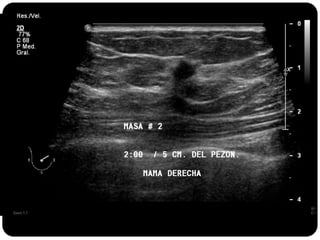

Paciente femenina de 66 años con historia clínica de 1er gesta antes de los 30 años y antecedentes de lactancia positiva, presenta una lesión palpable en la mama derecha. Los estudios radiológicos indican un diagnóstico de bi-rads 5, con biopsias revelando adenocarcinoma lobulillar infiltrante en la glándula mamaria derecha y adenocarcinoma ductal in situ en la izquierda. El caso fue evaluado por las doctoras Jacqueline Preciado Vargas y Beatriz E. González Ulloa.